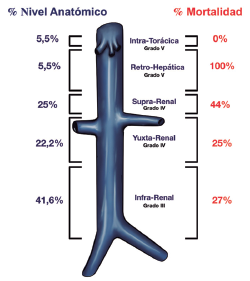

Ramiro Fernando Navarrete Castillo, José Reinaldo Leiva Flores, Jorge Isaac Ramírez Rivera

|

|

|